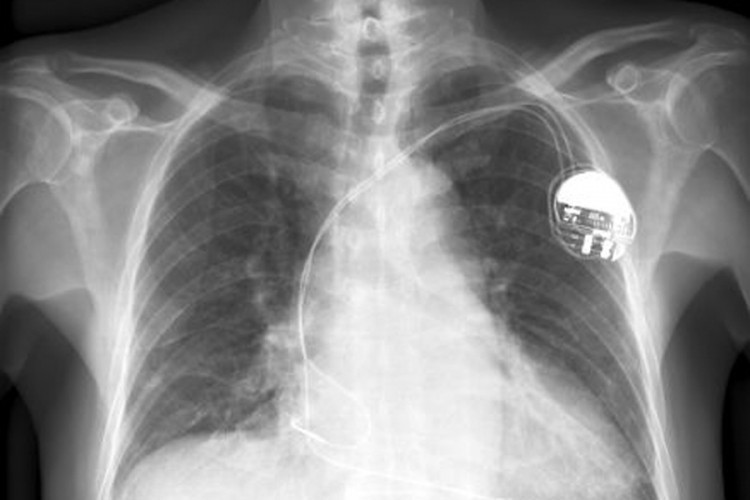

"MacRumors" je u nedavnom izvještaju spomenuo nedavno ažurirani dokument zakopan u bazi Appleovih službenih uputstava i savjeta u kojem kompanija predlaže da korisnici drže iPhone barem 15.24 centimetara (6 inča) od pejsmejkera ili bilo koje vrste sličnih implanata poput defibrilatora. Ako se uređaj nalazi na punjaču, udaljenost se treba povećati na 30 centimetara.

Appleovo dodavanje upozorenja i Medtronicova izjava stižu kratko nakon objave studije u kojoj je naulnik uspio deaktivirati pacijetnov ugrađeni defibrilator držeći iPhone 12 direktno iznad uređaja. Valja takođe naglasiti da je studija sprovedena samo na jednoj osobi i nije dokazala hoće li se isto dogoditi ako se srcu približi bilo koji drugi telefon, kamoli iPhone 12 opremljen MagSafeom.

Deaktiviranje ugrađenih zdravstvenih uređaja u blizini jakih magneta nije ništa novo - štaviše, na to naučnici upozoravaju već godinama. Implantati su programirani da se ugase ukoliko prepoznaju blizinu jakog magneta, a doktori sve pacijente upozoravaju da nakon ugradnje moraju jako paziti na blizinu mobilnih telefona i drugih uređaja koji generiraju jako magnetskoj polje.